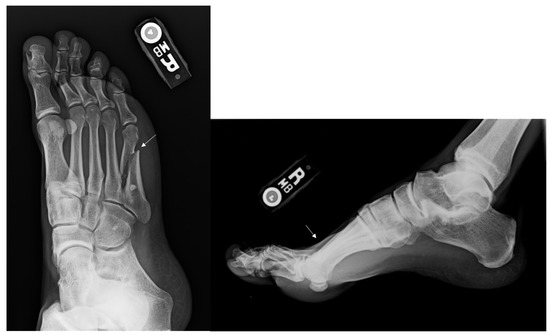

Figure 5.

Radiographs of a Metatarsal Fracture Angulated greater than 10 degrees. Displayed above are radiographs of second, third and fourth metatarsal fractures with angulation greater than 10 degrees. The arrows above identify the central metatarsal fractures.

Six out of 38 fractures presented with angulation greater than 10 degrees. (Figure 5) One of these 6 fractures was treated non-operatively and healed uneventfully. Three of the 5 patients treated operatively with greater than 10 degrees of initial angulation were unable to return to running and were eventually medically discharged from the military.